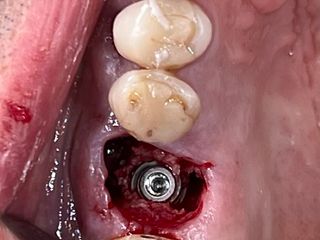

6. Immediate implant placement Ø 6.4mm Axiom® X3, 4 mm deep from the gum margin in the bone furcation for mucointegration.

6